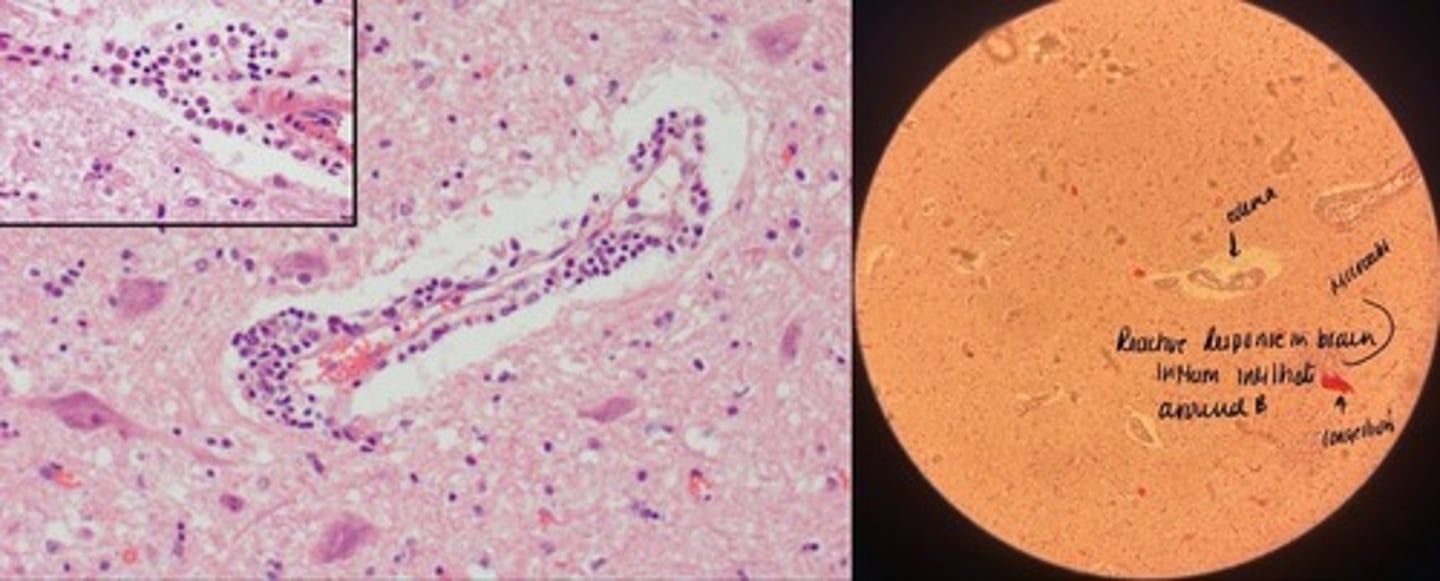

Non-purulent encephalitis

- perivascular cuffing w/ lymphocytes of congested vessel

- increased glial cells => glialosis rosettes

- focal neuronal loss

- increased plasma + macrophages

Purulent encephalitis

- congestion of bv + neuronal degen

- perivascular cuffing + edema

- microabscess in necrotic brain tissue

Eosinophilic encephalitis

- MANY eosinophils in perivascular space

- cerebral edema => empty space around bvs + neurons

- neuronal degen + necrosis